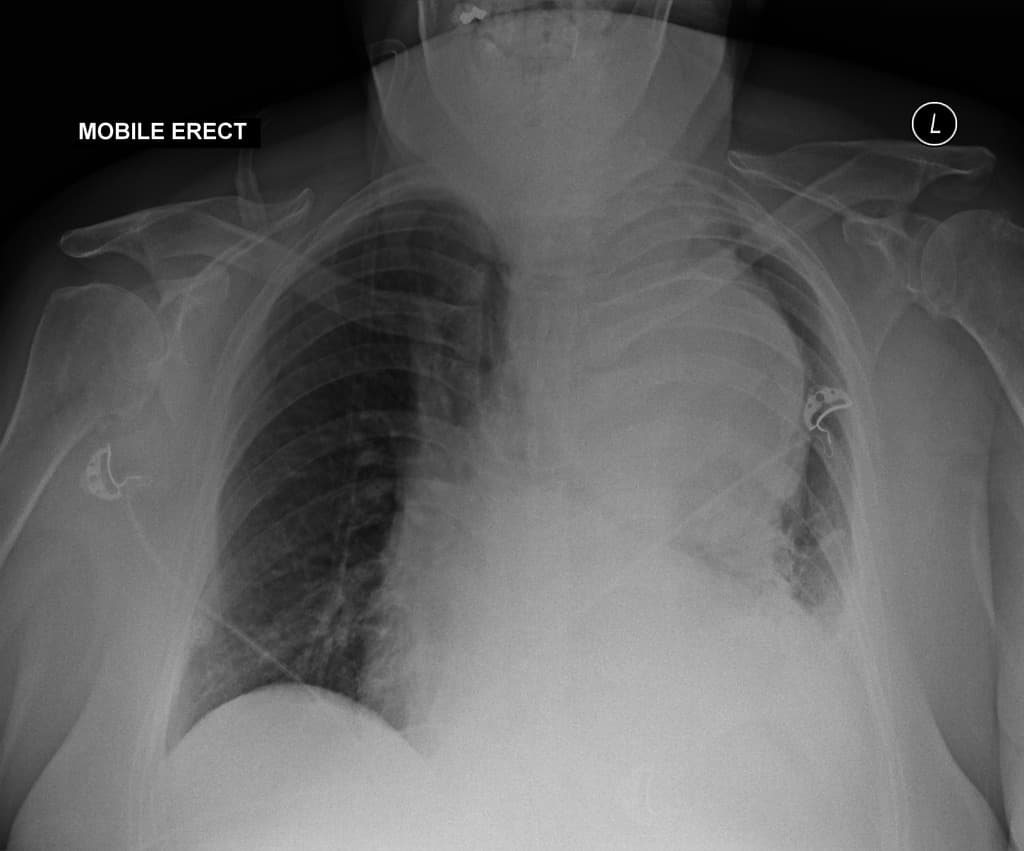

Bệnh nhân kêu đau ngực dữ dội.

- Phình tách động mạch chủ lan rộng (extensive aortic dissection), bắt đầu từ đoạn lên của động mạch chủ (ascending aorta) và tiếp tục dọc theo toàn bộ động mạch chủ xuống ổ bụng.

- Có vạt nội mạc (intimal flap) rõ ràng trên hình ảnh cắt lớp vi tính (CT), hiện diện ở động mạch chủ lên, cung động mạch chủ và động mạch chủ xuống, kéo dài đến động mạch chủ bụng.

- Phình tách liên quan đến các nhánh cung động mạch chủ, bao gồm động mạch thân cánh tay đầu (brachiocephalic artery), động mạch cảnh chung trái (left common carotid artery) và động mạch dưới đòn trái (left subclavian artery), với dấu hiệu hẹp lòng (narrowing) và giảm tưới máu (hypoperfusion) thứ phát.

- Phình tách lan xuống đến động mạch thận hai bên (bilateral renal arteries), gây hẹp đáng kể lòng mạch, phù hợp với thiếu máu cục bộ (ischemia) do giảm tưới máu thận.

- Không thấy hình ảnh huyết khối thành mạch (mural thrombus) lớn hoặc vỡ mạch (rupture), nhưng có dấu hiệu tràn dịch màng ngoài tim lượng nhỏ (small pericardial effusion), không phù hợp với tràn máu cấp (hemopericardium).

- Các động mạch vành xuất phát bình thường, không thấy phình tách lan vào động mạch vành.

- Không thấy giãn động mạch chủ (aortic aneurysm) trước đó; đường kính động mạch chủ lên khoảng 5,2 cm tại điểm rộng nhất.

- Không thấy tràn khí màng phổi (pneumothorax) hay tràn dịch màng phổi (pleural effusion) đáng kể.

- Các cấu trúc trung thất (mediastinum) bị xô lệch nhẹ do giãn và biến dạng động mạch chủ.

- Gan, lách, tụy và hai thận không có nhồi máu (infarction) rõ trên các pha tương phản (contrast phases), mặc dù thận trái có dấu hiệu tưới máu không đều, gợi ý giảm tưới máu bán phần.

- Không thấy hình ảnh phù phổi (pulmonary edema) hay xẹp phổi (atelectasis).

Phình tách động mạch chủ lan rộng đến động mạch thận và liên quan đến các nhánh cung chủ (extensive aortic dissection extending to renal arteries and involving arch branches), loại DeBakey I / Stanford A (nếu có hình ảnh động mạch chủ lên bị liên quan).

Trường hợp này mô tả một phình tách động mạch chủ lan rộng bắt nguồn từ đoạn lên, lan xuống qua cung động mạch chủ và động mạch chủ ngực xuống đến động mạch chủ bụng, liên quan đến các nhánh lớn và động mạch thận hai bên. Sự hiện diện của vạt nội mạc trên CT xác nhận chẩn đoán. Do có tổn thương đoạn lên, đây là loại Stanford A (loại DeBakey I nếu bắt nguồn từ đoạn lên và lan xuống), có nguy cơ cao xảy ra các biến chứng như chèn ép tim, vỡ động mạch chủ và hội chứng thiếu máu tưới các cơ quan. Cần can thiệp phẫu thuật khẩn cấp để ngăn ngừa tử vong. Tổn thương động mạch thận có thể dẫn đến tăng huyết áp do nguyên nhân động mạch thận hoặc suy thận cấp, và đặt stent nội mạch có thể được xem xét trong một số trường hợp. Theo dõi hình ảnh học là cần thiết để đánh giá tiến triển bệnh và độ bền của stent sau điều trị.